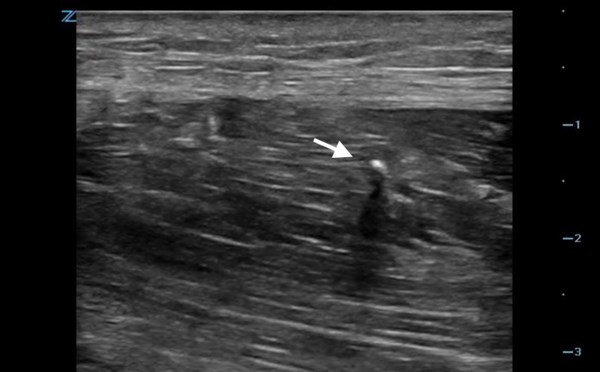

Foreign Body Localization